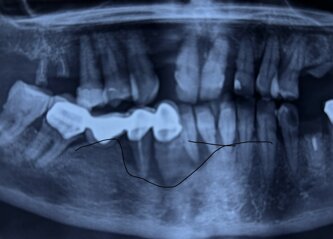

RIGENERAZIONE OSSEA GUIDATA

RIASSORBIMENTO OSSEO GRAVE

Radiografia panoramica che mostra un riassorbimento osseo alveolare diffuso secondario a parodontopatia cronica generalizzata.

La perdita ossea interessa prevalentemente le aree interprossimali, con riduzione dell’altezza crestale variabile, compatibile con una compromissione significativa del supporto parodontale.